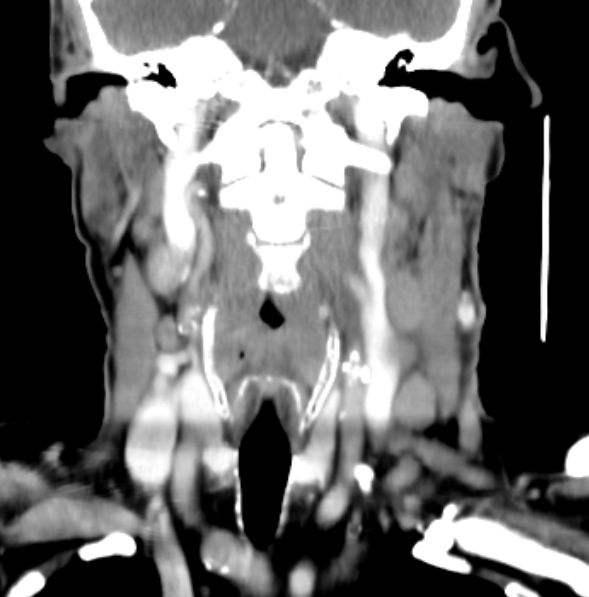

64-jähriger Mann mit tumoröser Raumforderung der linken Tonsille. Die primäre Histologie war verdächtig auf ein entdifferenziertes p16-positives Plattenepithelkarzinom. Bei der Radikaloperation wurden 84 Lymphknoten der Level 2-4 beiderseits entfernt, von denen 55 metastatisch befallenen waren. Zusätzlich wurde ein nicht zugänglicher Lymphknoten unterhalb der Karina festgestellt. Die transösophageale Punktion dieses Lymphknotens ergab den Verdacht eines malignen Lymphoms. Daraufhin wurden von den zervikalen Lymphnoten zusätzliche immunhistochemische Untersuchungen durchgeführt. Nach Vorliegen der Referenzpathologie handelt es sich um den seltenen Fall eines sarkomatoiden Lymphom oder eines histiozytischen Sarkoms. Diese Zellen sehen einem entdifferenzierten Plattenepithelkarzinom sehr ähnlich. | ||

Zahlreiche vergrößerte zervikale Lymphknoten.![]() |